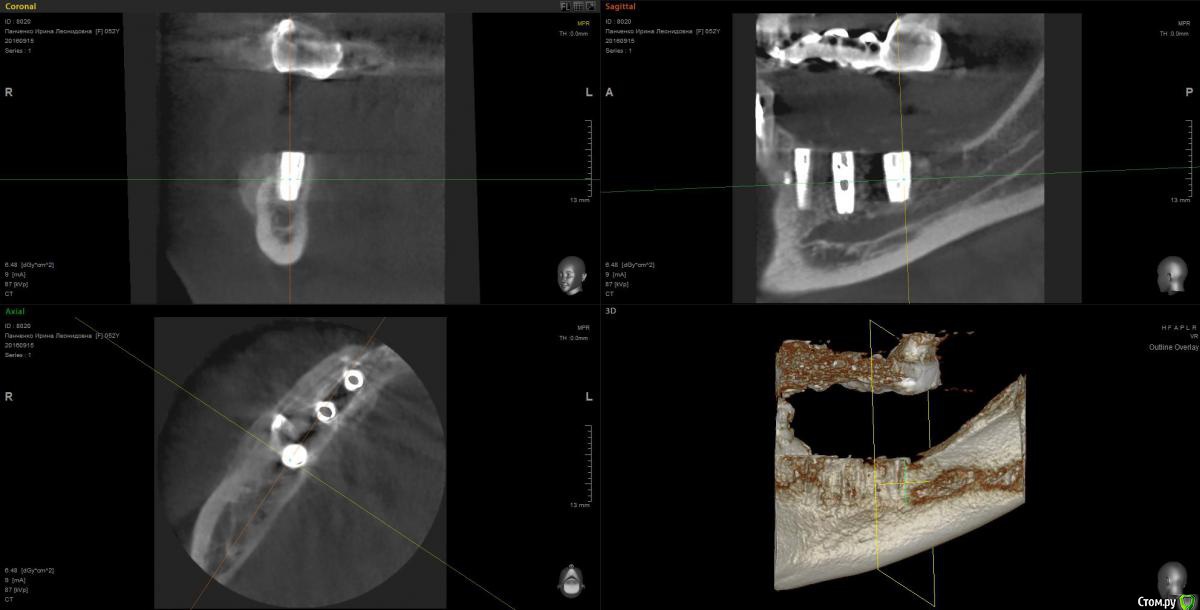

Kostoprav Опубликовано 13 марта, 2017 Поделиться Опубликовано 13 марта, 2017 рецепт сосиски: 70%биопласт by владмива +30%аутокость, мембрана hyprosorb кт до кт сразу после имплантации кт через пол года 3 Ссылка на комментарий

Kostoprav Опубликовано 14 марта, 2017 Автор Поделиться Опубликовано 14 марта, 2017 по порядку 8 Ссылка на комментарий